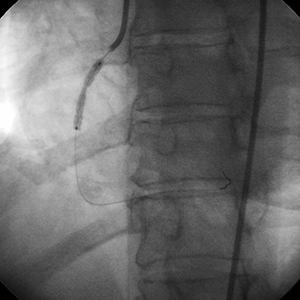

• 3.5 mm and 4 mm high pressure balloons were used post stent deployment

• High pressure balloons were unsuccessful in expanding the stent

This highly stenosed RCA contained a significant degree of calcium that could not be fully appreciated at the time of the angiography. It should be noted that the calcified segment was not in the region of the most critical narrowing. However, the calcified lesion was undilatable after stent deployment.

If pre-dilation of the vessel had been performed prior to stent deployment, the need for using the Rotablator System would have been made obvious, potentially avoiding the difficulty encountered in treating this vessel.